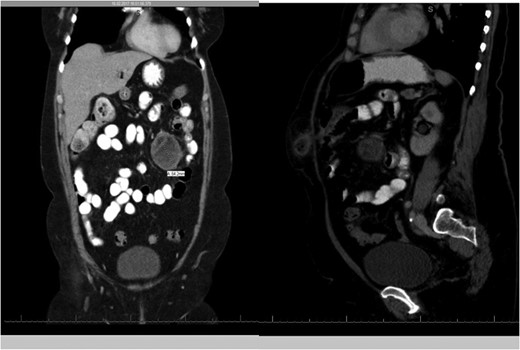

A 57-year-old woman was admitted to our institute (Spital Visp, Spitalzentrum Oberwallis) on 16 February 2017 with a suspected diagnosis of incarcerated port-site hernia following laparoscopic cholecystectomy 8 years ago. The port site hernia appeared 4 years ago and it was reducible without any obstructive symptoms. The patient initially consulted her general practitioner due to progressive pain and irreducible swelling at the site of the pre-existing hernia and was referred to us for further treatment. A CT scan revealed bowel contents and omentum in the hernial sac with an incidental finding of an around 6.5 cm in diameter mesenterial tumor in the jejunal area (Fig. 1).